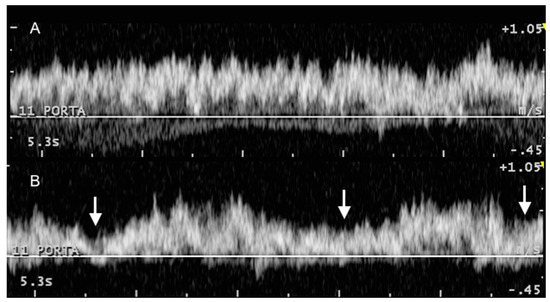

3.2. Portal System